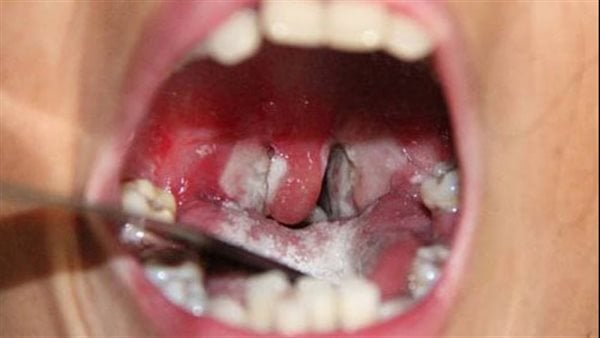

أفادت مصادر محلية ان سبعة أشخاص توفوا ببلدية تناها بمقاطعة كنكوصة في ولاية العصابة، وذلك جراء إصابتهم بمرض يرجح أنه الدفتيريا، فيما أصيب أكثر من 70 آخرين.

كما أكدت المصادر عدم تسجيل حالات جديدة في يومي الجمعة والسبت، مشيرا إلى أن من أخذوا الدواء تماثلوا للشفاء.